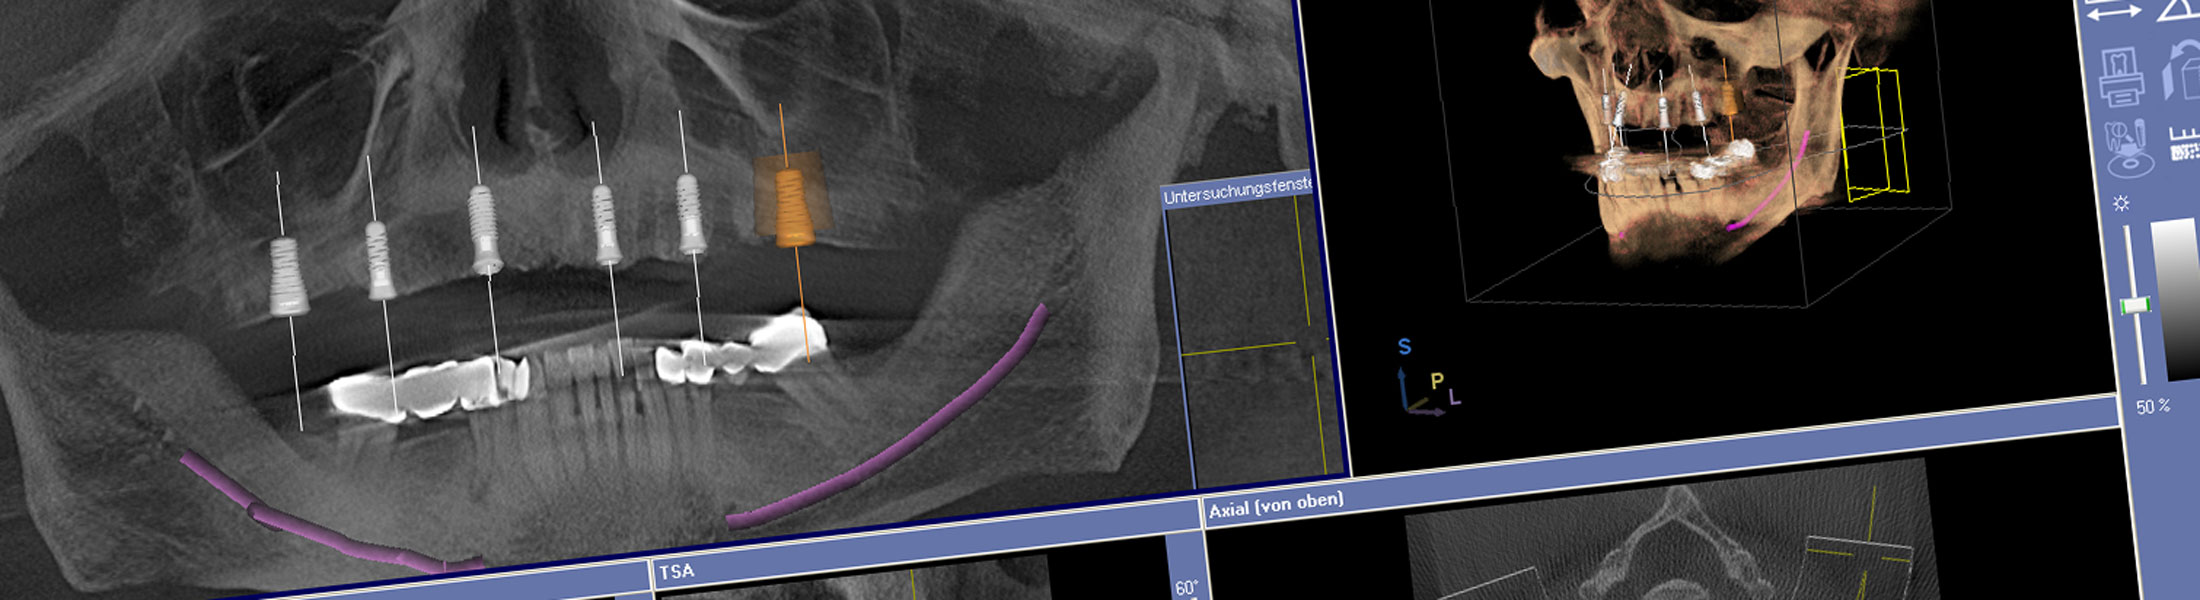

Die Digitale Volumentomographie ermöglicht zusammen mit unserer Implantationssoftware (Med 3d-Implant) eine computergestützte 3D-Planung unter anderem in der Implantologie. Sie unterstützt uns bei der Planung, der Auswahl eines geeigneten Implantat-Designs und der optimalen Implantat-Position. Unsere überweisenden Kollegen erhalten schon in der Planungsphase wichtige Informationen für eine bessere prothetische Versorgung von Implantaten.